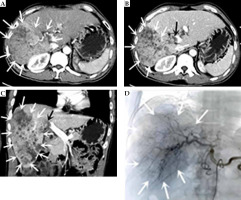

Fig. 1

Computed tomography (CT), DSA images before treatment. A) Cross section at CT arterial stage. B) Cross section at CT portal stage. C) CT portal stage (multiple hypodense lesions with irregular morphology and no obvious envelope seen in the right lobe of the liver, measuring approximately 16 cm × 9 cm. CT diagnosis showed (1) Diffuse hepatocellular carcinoma in the right lobe of liver, with invasion of the right branch of portal vein and part of the trunk, and (2) Mild cirrhosis. D) Angiography of DSA before treatment. DSA hepatic arteriography showed multiple blood-rich lesions in the right lobe of liver, without arterio-venous fistula or arterio-venous portal veins. The white arrow indicate the hepatocellular carcinoma lesion, and the black arrow is the portal carcinoma thrombus